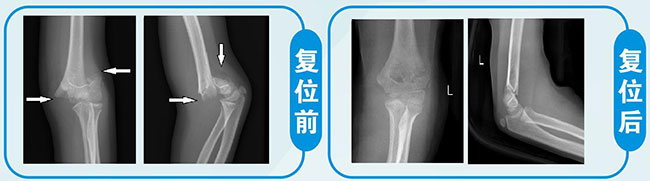

1、 儿童肱骨髁上骨折